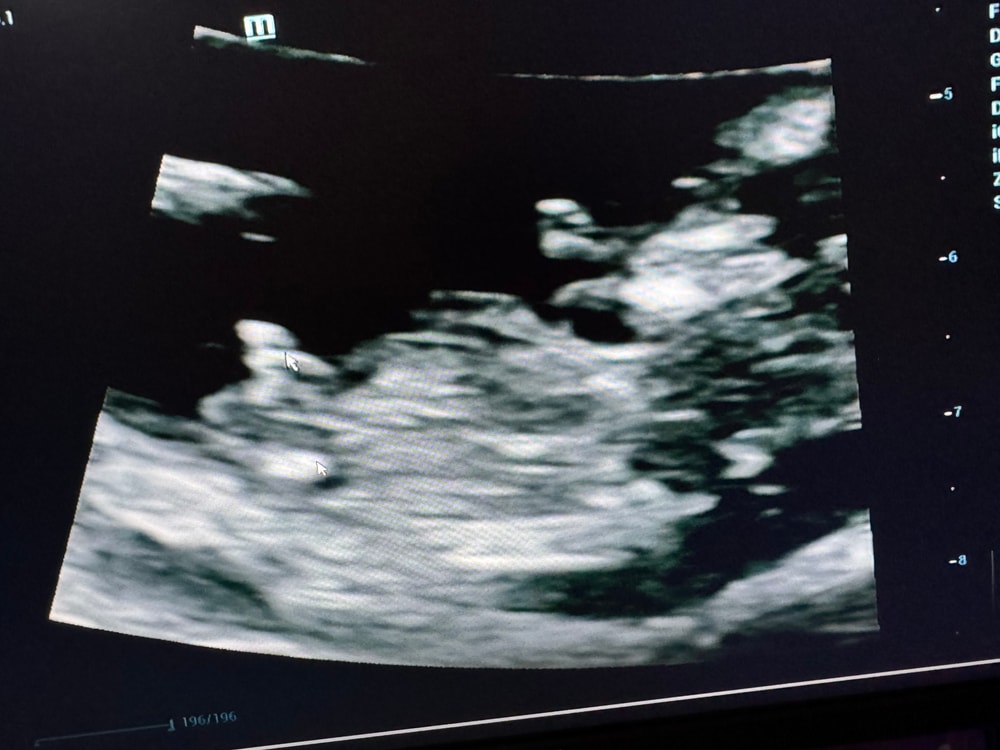

Всем привет , все хорошо , сердце бьется ,человек растет 😁 следующее узи 8.04.25 и на учет вставать.